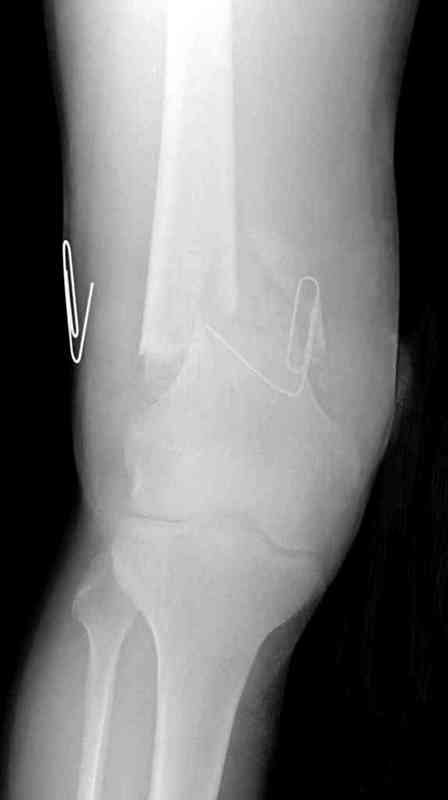

Больная К. с тугим ложным суставом н/3 бедра. Травма в 2005 г.-закрытый перелом, остеосинтез в аппарате Илизарова. В 2006 г. оперирована по поводу несросшегося перелома.

В ноябре 2006 г. демонтаж аппарата, после чего в течении месяца развилась вальгусная деформация. Имеется патологическая подвижность. Объем движений в коленном суставе 180-140. На обсуждение выносятся варианты лечения погружными конструкциями.

The patient with non-union of the distal femur. Trauma in 2005 - closed fracture of the femur, external fixation with Ilizarov apparatus. Non-union. In 2006 open reduction and external fixation with Ilizarov apparatus. In November 2006 the apparatus was removed, after that valgus deformation developed. There is pathological mobility. The knee motion 180-140. We'd like to discuss options of internal fixation.

Надо все-таки разобраться, что там местно - по снимку какое-то как будто сращение на ограниченном участке, но, как пишут, есть и патологическая подвиижность...

Если там сращние или тугой ожный сустав - можно лечить закрыто. Подправить аппаратом и либо заштифтовать, либо пластинку, можно с пластикой, Если дело ближе к болтающемуся ложному суставу - тогда открытая адаптация, аутопластика, как Михаил написал.

Согласен. По снимкам не похоже, чтоб сильно болталось, скорее даже срослось. Клинически с таким коротким фрагментом трудно оценить где "болтается" - в переломе или в суставе. Эффективно смотреть под ЭОПом в режиме скопии.